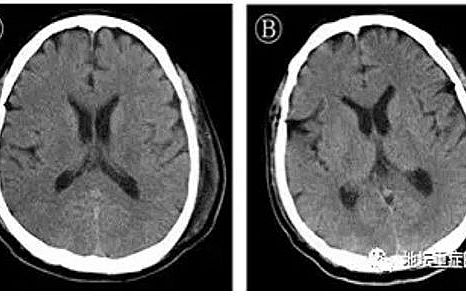

Dịch Covid-19: Lần đầu tiên phát hiện virus SARS-CoV-2 có thể tấn công hệ thần kinh trung ương

Lần đầu tiên chứng minh rằng, virus SARS-CoV-2 có thể làm tổn thương hệ thần kinh trung ương của bệnh nhân.